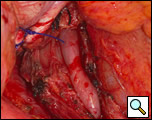

The surgical approach is a left posterolateral thoracotomy, entering the chest over the bed of the unresected 7th or 8th rib. On entering the thoracic cavity, the pulmonary ligament is divided and the lung is packed out of the way superiorly. The epiphrenic diverticulum is often found at the level of the inferior pulmonary vein. The pleura over the esophagus is divided allowing the esophagus to be gently mobilized. Penrose drains are used to encircle the esophagus superior and inferior to the diverticulum to facilitate the dissection (Figure 3). The diverticulum often arises to the right side necessitating rotation of the esophagus to clearly visualize the neck of the diverticulum. The diverticulum and its base are carefully dissected from the adjacent esophagus (Figure 4). Both vagus nerves are clearly identified and preserved during this maneuver. Once the diverticulum base is defined, a 40 Fr bougie is introduced across the gastroesophageal junction. This is performed under direct vision with the surgeon closely monitoring the safe passage of the bougie.

The diverticulum is then amputated at its base with a TA-60, 4.8 stapling device (Figure 5). The staple line is kept parallel to the long axis of the esophagus to avoid tension and decrease the risk of leak (Figure 6). The diverticulum is amputated sharply with a scalpel (Figure 7) and the staple line reinforced by approximating the muscularis with interrupted 3-0 silk sutures (Figure 8).